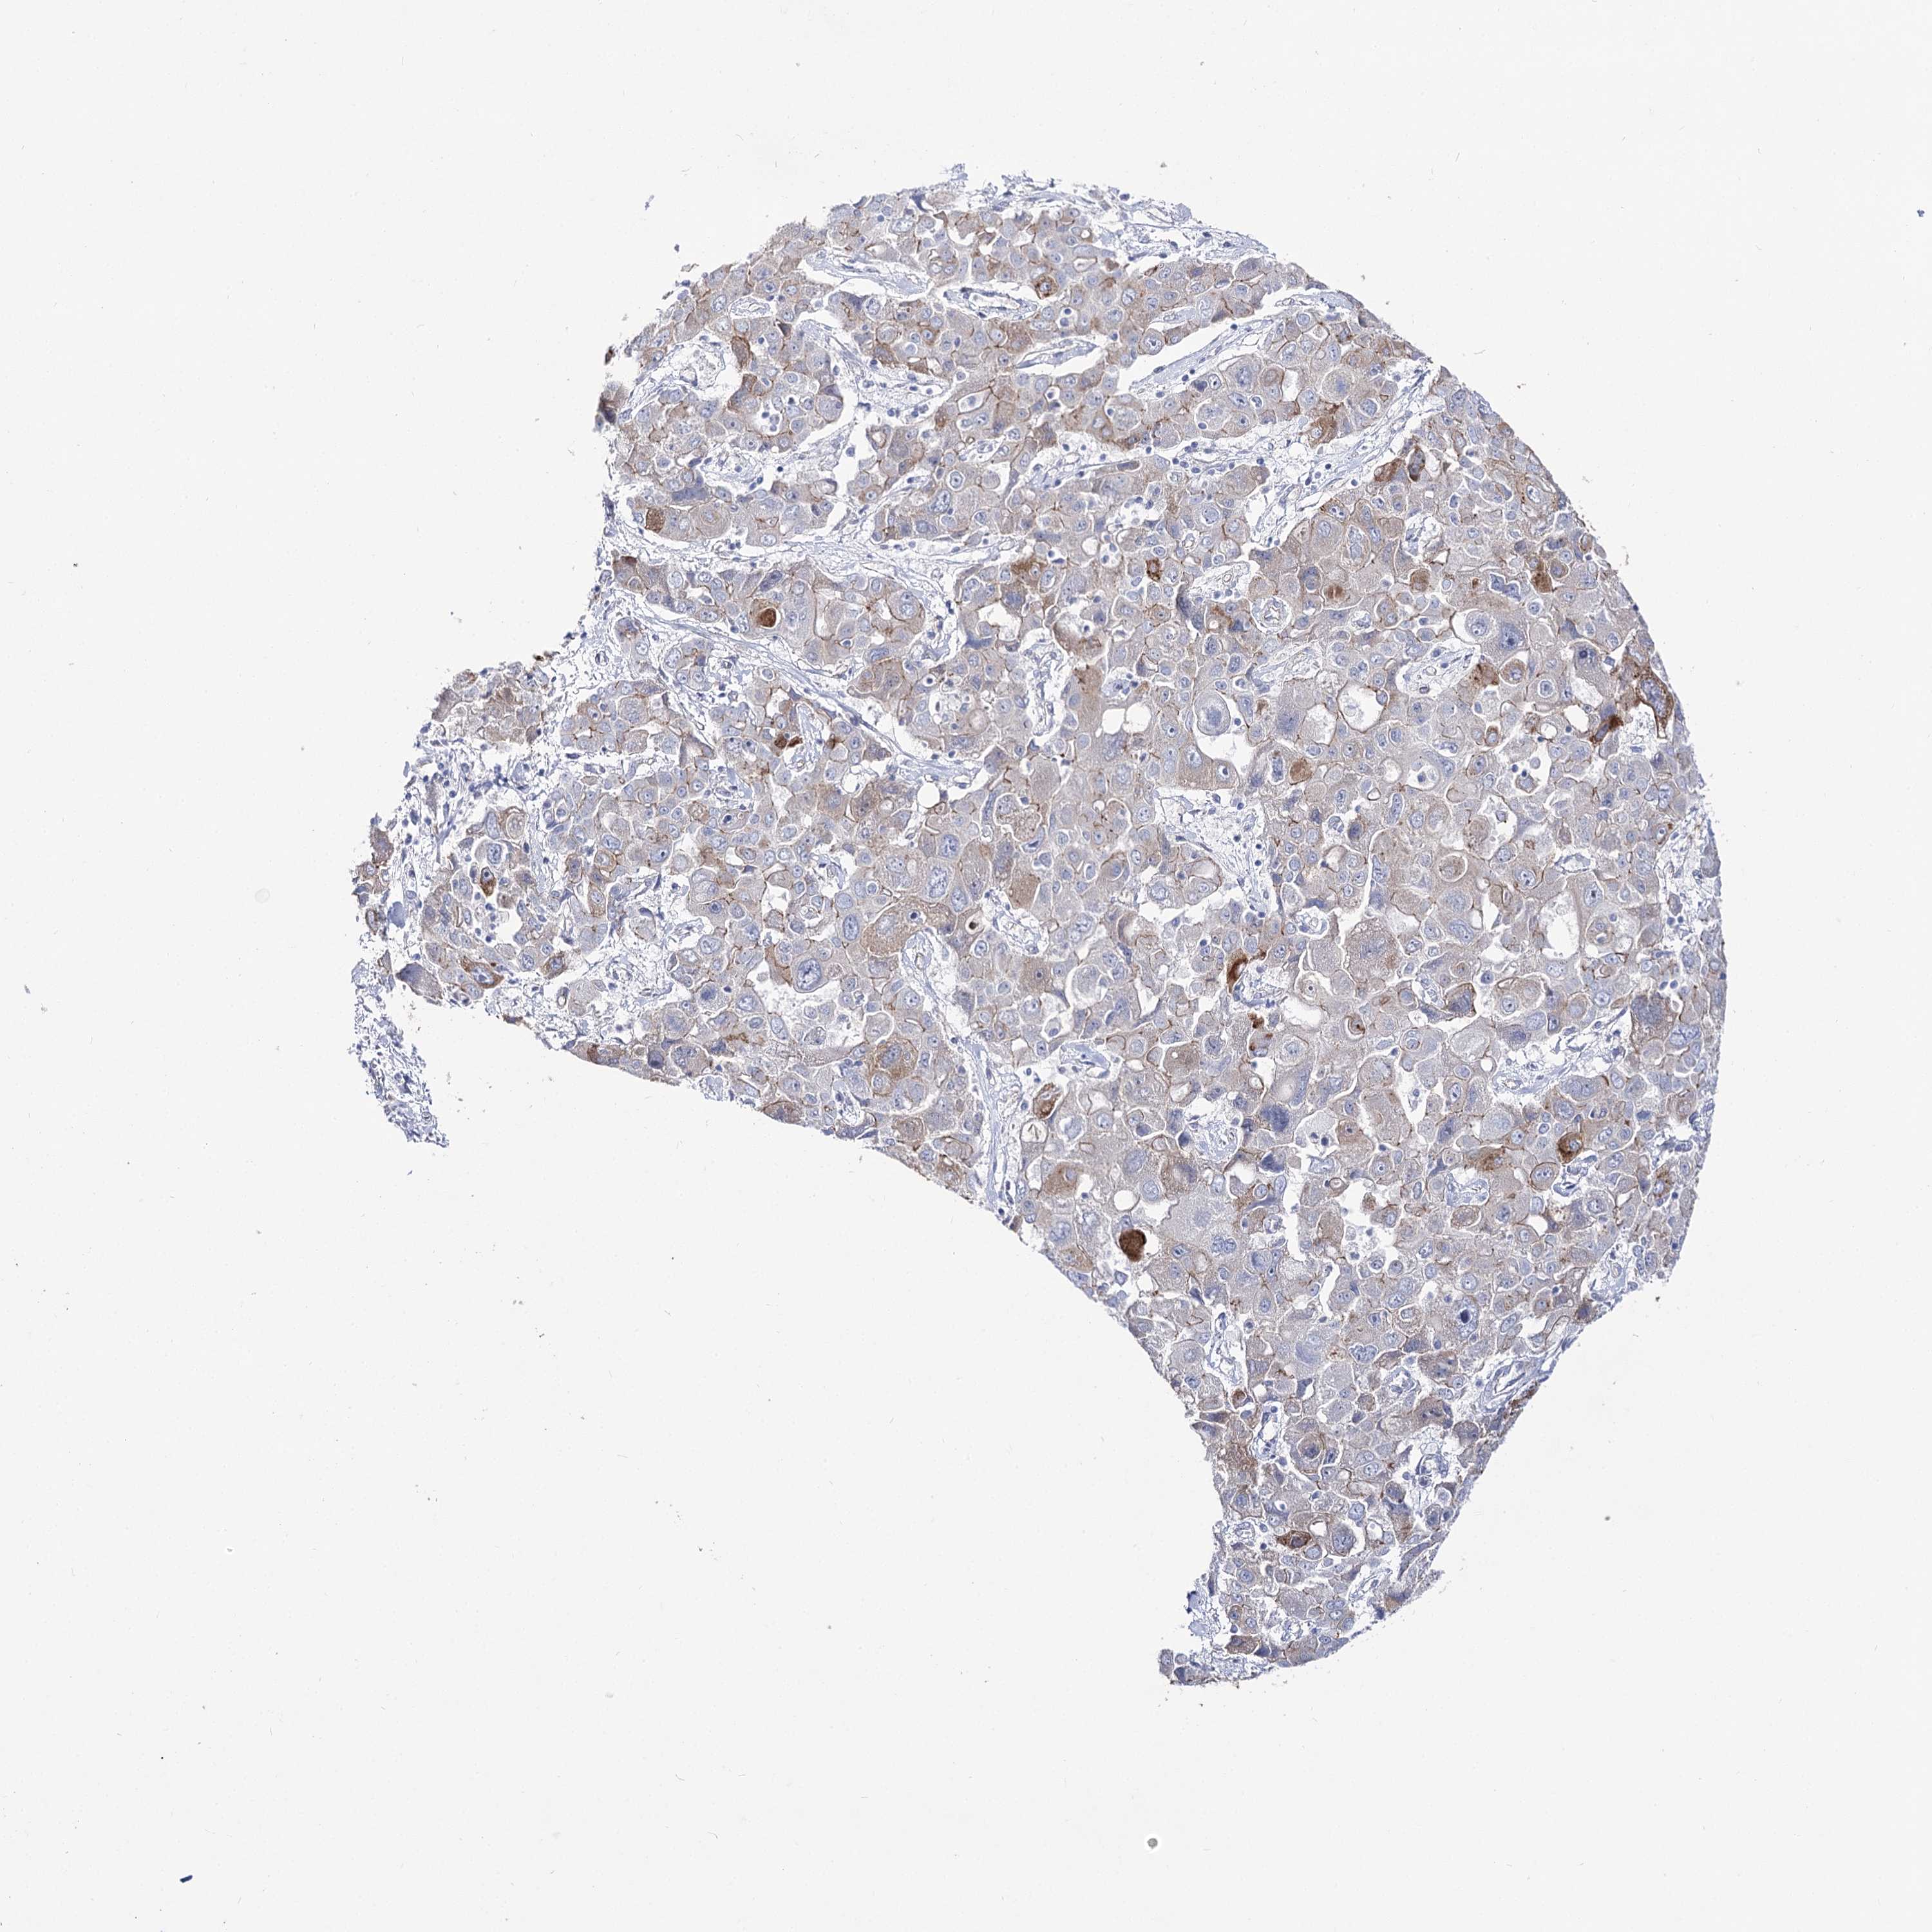

LIVER CANCER - Protein expressioni

A mouse-over function shows sample information and annotation data. Click on an image to view it in a full screen mode. Samples can be filtered based on level of antibody staining by selecting one or several of the following categories: high, medium, low and not detected. The assay and annotation is described here.

Note that samples used for immunohistochemistry by the Human Protein Atlas do not correspond to samples in the TCGA dataset.

Antibody stainingi

Antibody staining in the annotated cell types in the current human tissue is reported as not detected, low, medium, or high, based on conventional immunohistochemistry profiling in selected tissues. This score is based on the combination of the staining intensity and fraction of stained cells.

Each image is clickable and will lead to virtual microscopy that enables deeper exploration of all samples and also displays staining intensity scores, fraction scores and subcellular localization as well as patient and tissue information for each sample.

Antibody HPA037953

Antibody HPA037954

Staining

High

Medium

Low

Not detected

Intensity

Strong

Moderate

Weak

Negative

Quantity

>75%

75%-25%

<25%

None

Location

Nuclear

Cytoplasmic/membranous

Cytoplasmic/membranous,nuclear

Cholangiocarcinoma

Carcinoma, Hepatocellular, NOS